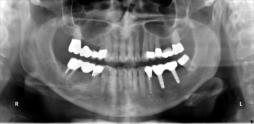

Beispiele für komplexe implantologische Versorgungen aus unserer Gemeinschaftspraxis

(Planung / Endversorgung -- als Röntgenaufnahmen)

C1

C2

C3